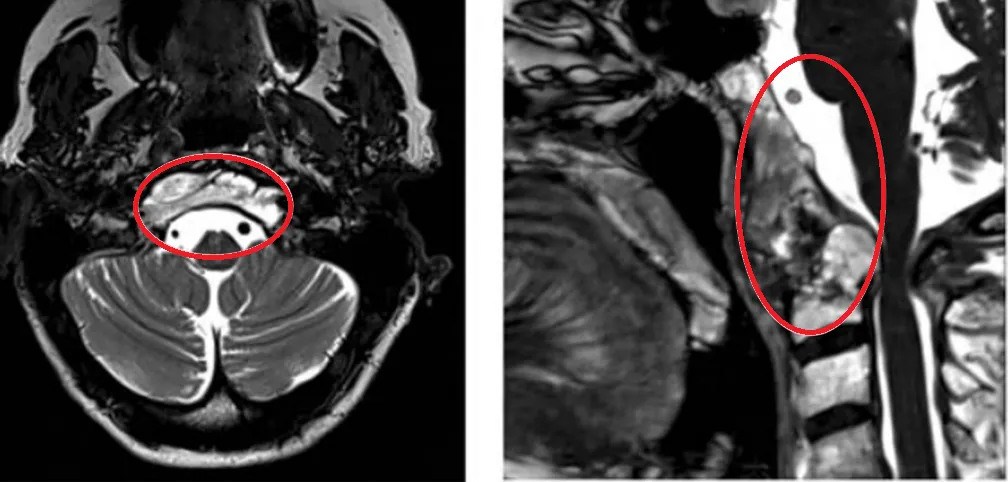

21岁法国女孩,出现颈部疼痛,MRI检查显示肿瘤集中在枕骨大孔和颅颈交界区的内部,病变拓展至硬膜内,累及双侧椎动脉。该名脊索瘤患者还伴有明显的骨质损害和硬膜内延伸。

术前MRI